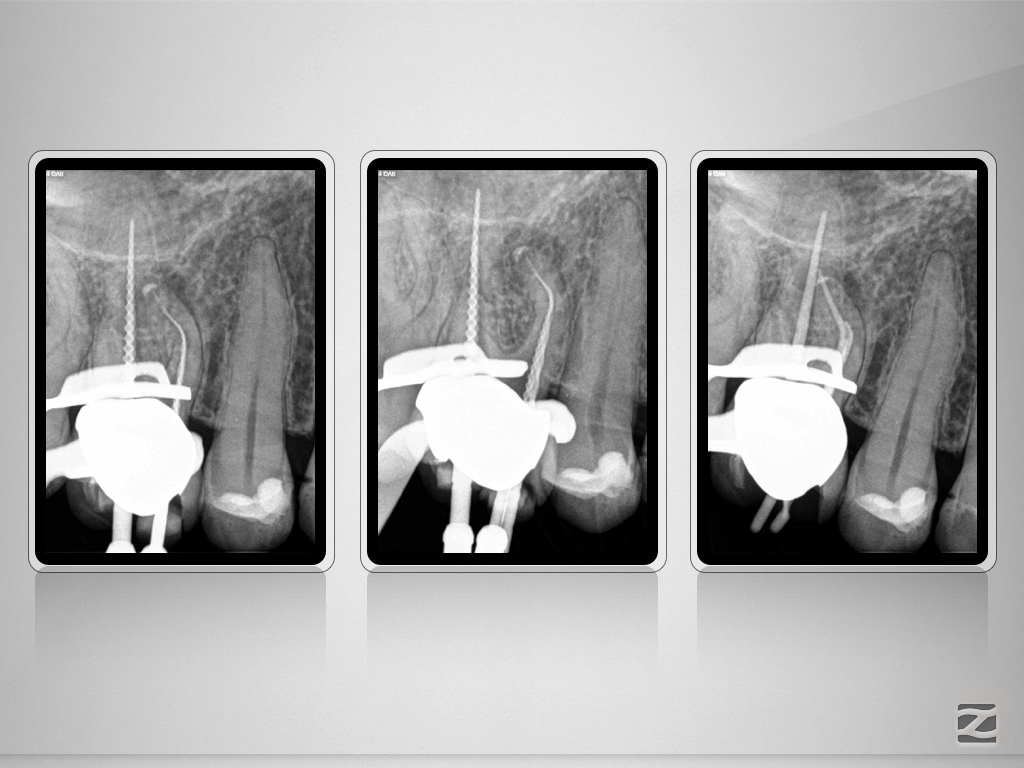

16D.008

Von allem etwas …